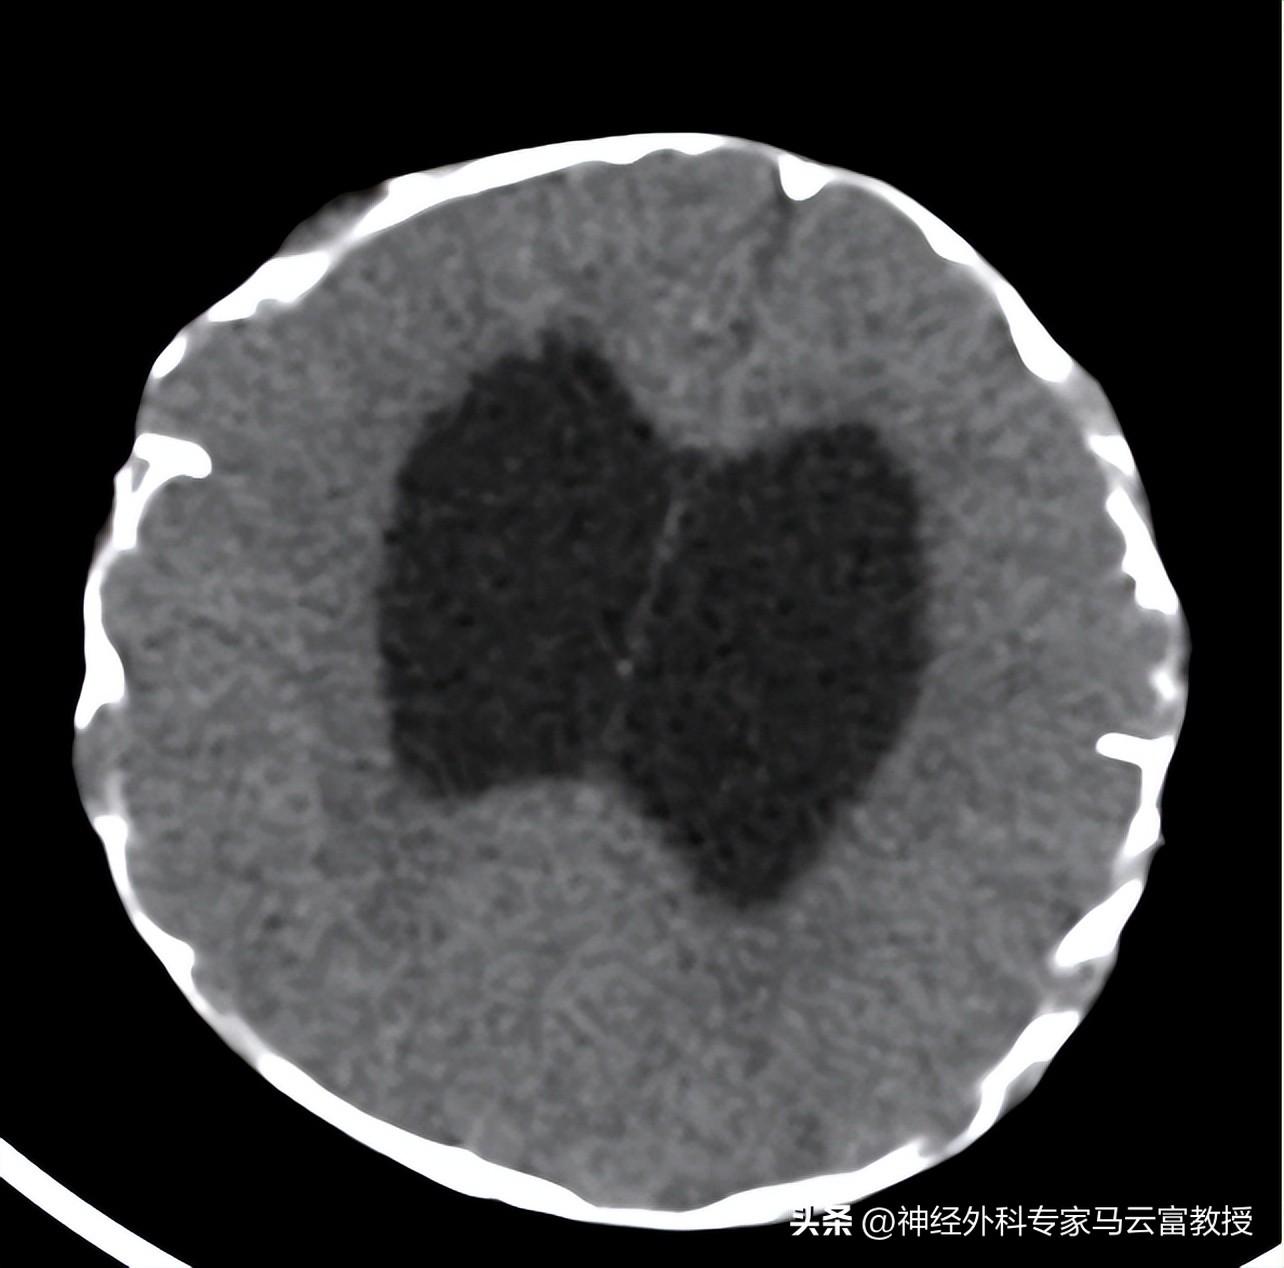

爲進一步明確病情,我院整合多學科資源,結合患兒既往門診檢查資料及入院後完善的各項檢查結果綜合研判。2025年12月15日,湖北省婦幼保健院顱腦CT薄層平掃報告提示:1、顱縫早閉,顱骨及顱腦形態發育異常;2、幕上腦室積水擴張,腦外間隙變窄,小腦扁桃體下疝,腦灰白質分界欠清晰,建議進一步行MRI檢查;3、掃描所及齶裂,眼眶相對較大、眼球稍外突。

顱腦CT-3D體層成像